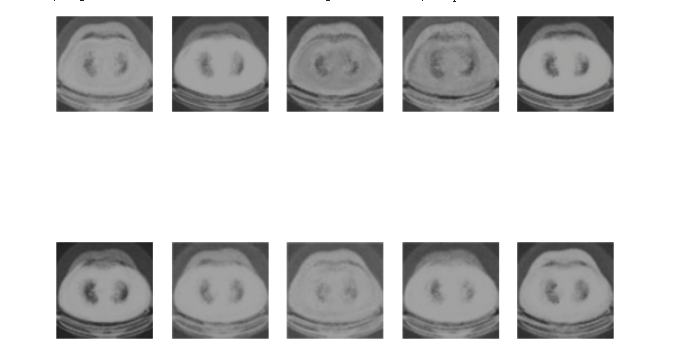

Figure 2. The generated image by VAE.

Through this structure, this study provided a systematic approach to employing VAEs for medical image generation, laying a robust foundation for future research and applications. Figure 2 shows the medical image of lung cancer generated by the VAEs model.

Figure 3. The medical images generated by the diffusion model.

Through the structured delineation above, we've vividly showcased how to leverage the controlled diffusion model technique for medical image data handling, aimed at enhancing image quality and eliminating noise. This lays a robust foundation for subsequent research and applications in medical imagery. Figure 3 shows the medical image of lung cancer generated by the Diffusion model.

For the lung cancer pictures generated by the VAE model, it can be found out by observing the picture Figure 2. The picture is more blurred than the original version. It can be observed that a lung cancer on the picture, but it basically can't see too many details. However, the VAE model generates images faster, and the average time to complete an Epoch is about 20 seconds (Figure 4), and it can be mass-produced quickly.

By observing the image generated by the diffusion model, it can be observed that it has more and better details, and it only uses 10 Epoch for training shown in Figure 5. It almost perfectly imitates the original image, although it has a huge flaw, that is the generation speed is very slow.

Results of Image Quality and Details. VAE: The images generated by the VAE, as seen in Figure 2, were comparatively blurrier and lacked the intricate details seen in the original images. However, the VAE was able to roughly capture the primary feature of lung cancer, presenting a decent approximation.

Diffusion Model: The diffusion model-generated images, depicted in Figure 3, showcased superior fidelity. These images retained a significant amount of the details seen in the original lung cancer CT scans, thereby demonstrating its ability to generate more clinically useful images.